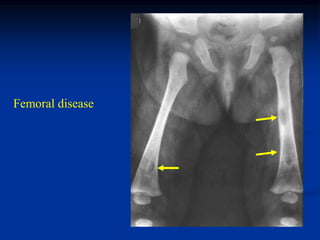

Femoral disease

Photomic